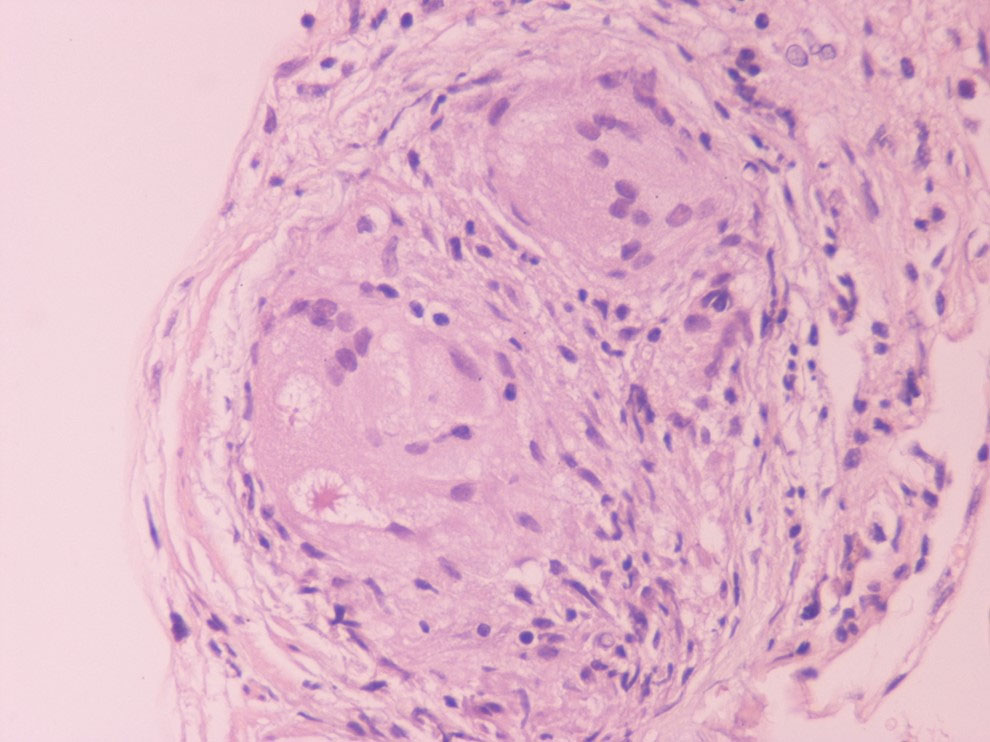

The incidence of progressive heart failure, arrhythmias and sudden cardiac death (SCD) increases as CS becomes clinically recognizable; thus, early diagnosis and initiation of therapy is crucial to improve prognosis (Dubrey and Falk, 2010; Kim et al., 2009; Mantini et al., 2012; Pierre-Louis et al., 2009; Voortman et al., 2019). The classic triad of criteria establishing a diagnosis of sarcoidosis is 1) a compatible clinical and/or radiological picture; 2) histological evidence of noncaseating granulomas and 3) exclusion of other diseases (Costabel, 2001; Hunninghake et al., 1999). Diagnosis usually requires a multi-disciplinary approach, as almost any organ may be affected; sarcoidosis is a diagnosis of exclusion, so establishing a CS diagnosis may be challenging (Bargagli and Prasse, 2018). Histological confirmation of CS cases is difficult, as endomyocardial biopsy (EMB) has low sensitivity (36%) due to the patchy nature of sarcoidosis and is also a procedure that is difficult to perform. Thus, cardiac sarcoidosis cannot be ruled out with a negative endomyocardial biopsy result (From et al., 2011; Uemura et al., 1999). Immunohistochemistry using anti-monoclonal antibody against P. acnes has even been suggested as a potential additive diagnostic tool given the low sensitivity of EMB (Asakawa et al., 2017). A more promising tool may be the recognition of increased lymphatic vessel counts on myocardial biopsy of CS subjects in the absence of granuloma, a finding that increases the sensitivity of EMB at 75% (Oe et al., 2019). Further, an immunohistochemical finding of increased dendritic cells along with decreased M2 among all macrophages in non-granulomatous sections of cardiac biopsy showed high specificity for cardiac sarcoidosis diagnosis, suggesting this phenotype as a histopathological surrogate for CS (Honda et al., 2016). A well-formed non-necrotizing granuloma in the heart is shown in Fig. 1.

Fig. 1.

Fig. 1.A well-formed non-necrotizing granuloma in the heart (Hematoxylin Eosin x400).